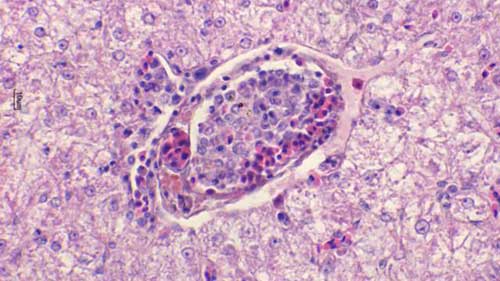

錐體蟲(chóng)